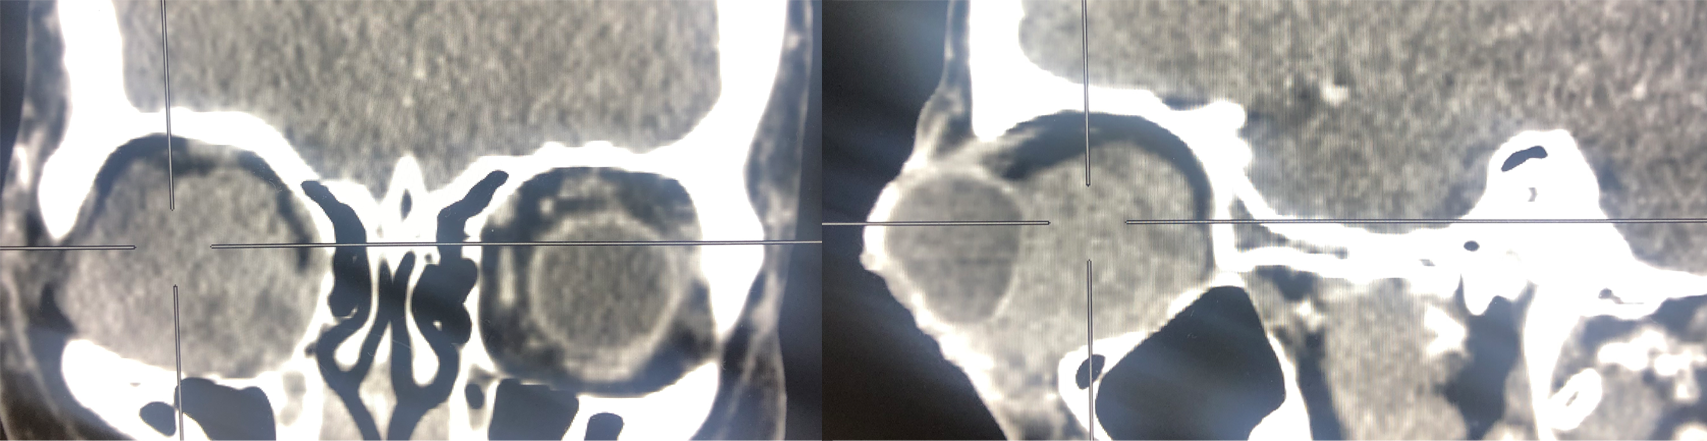

BeforeAfterAdvanced treatment for orbital conditions